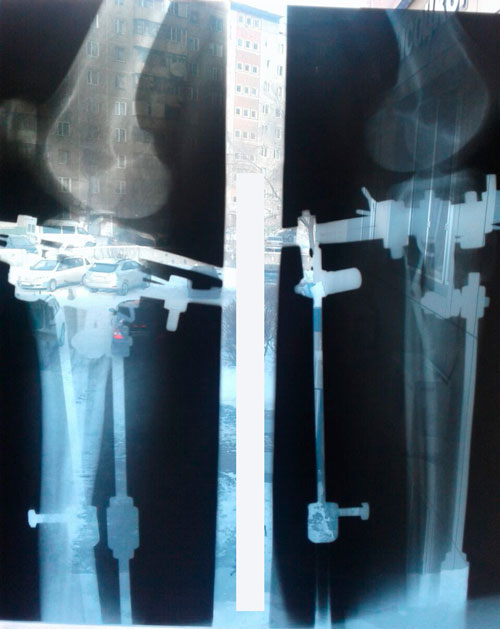

Дата операции 20.12.2016г.

Дата снятия аппаратов 04.03.2017г.

Срок лечения 71 день.